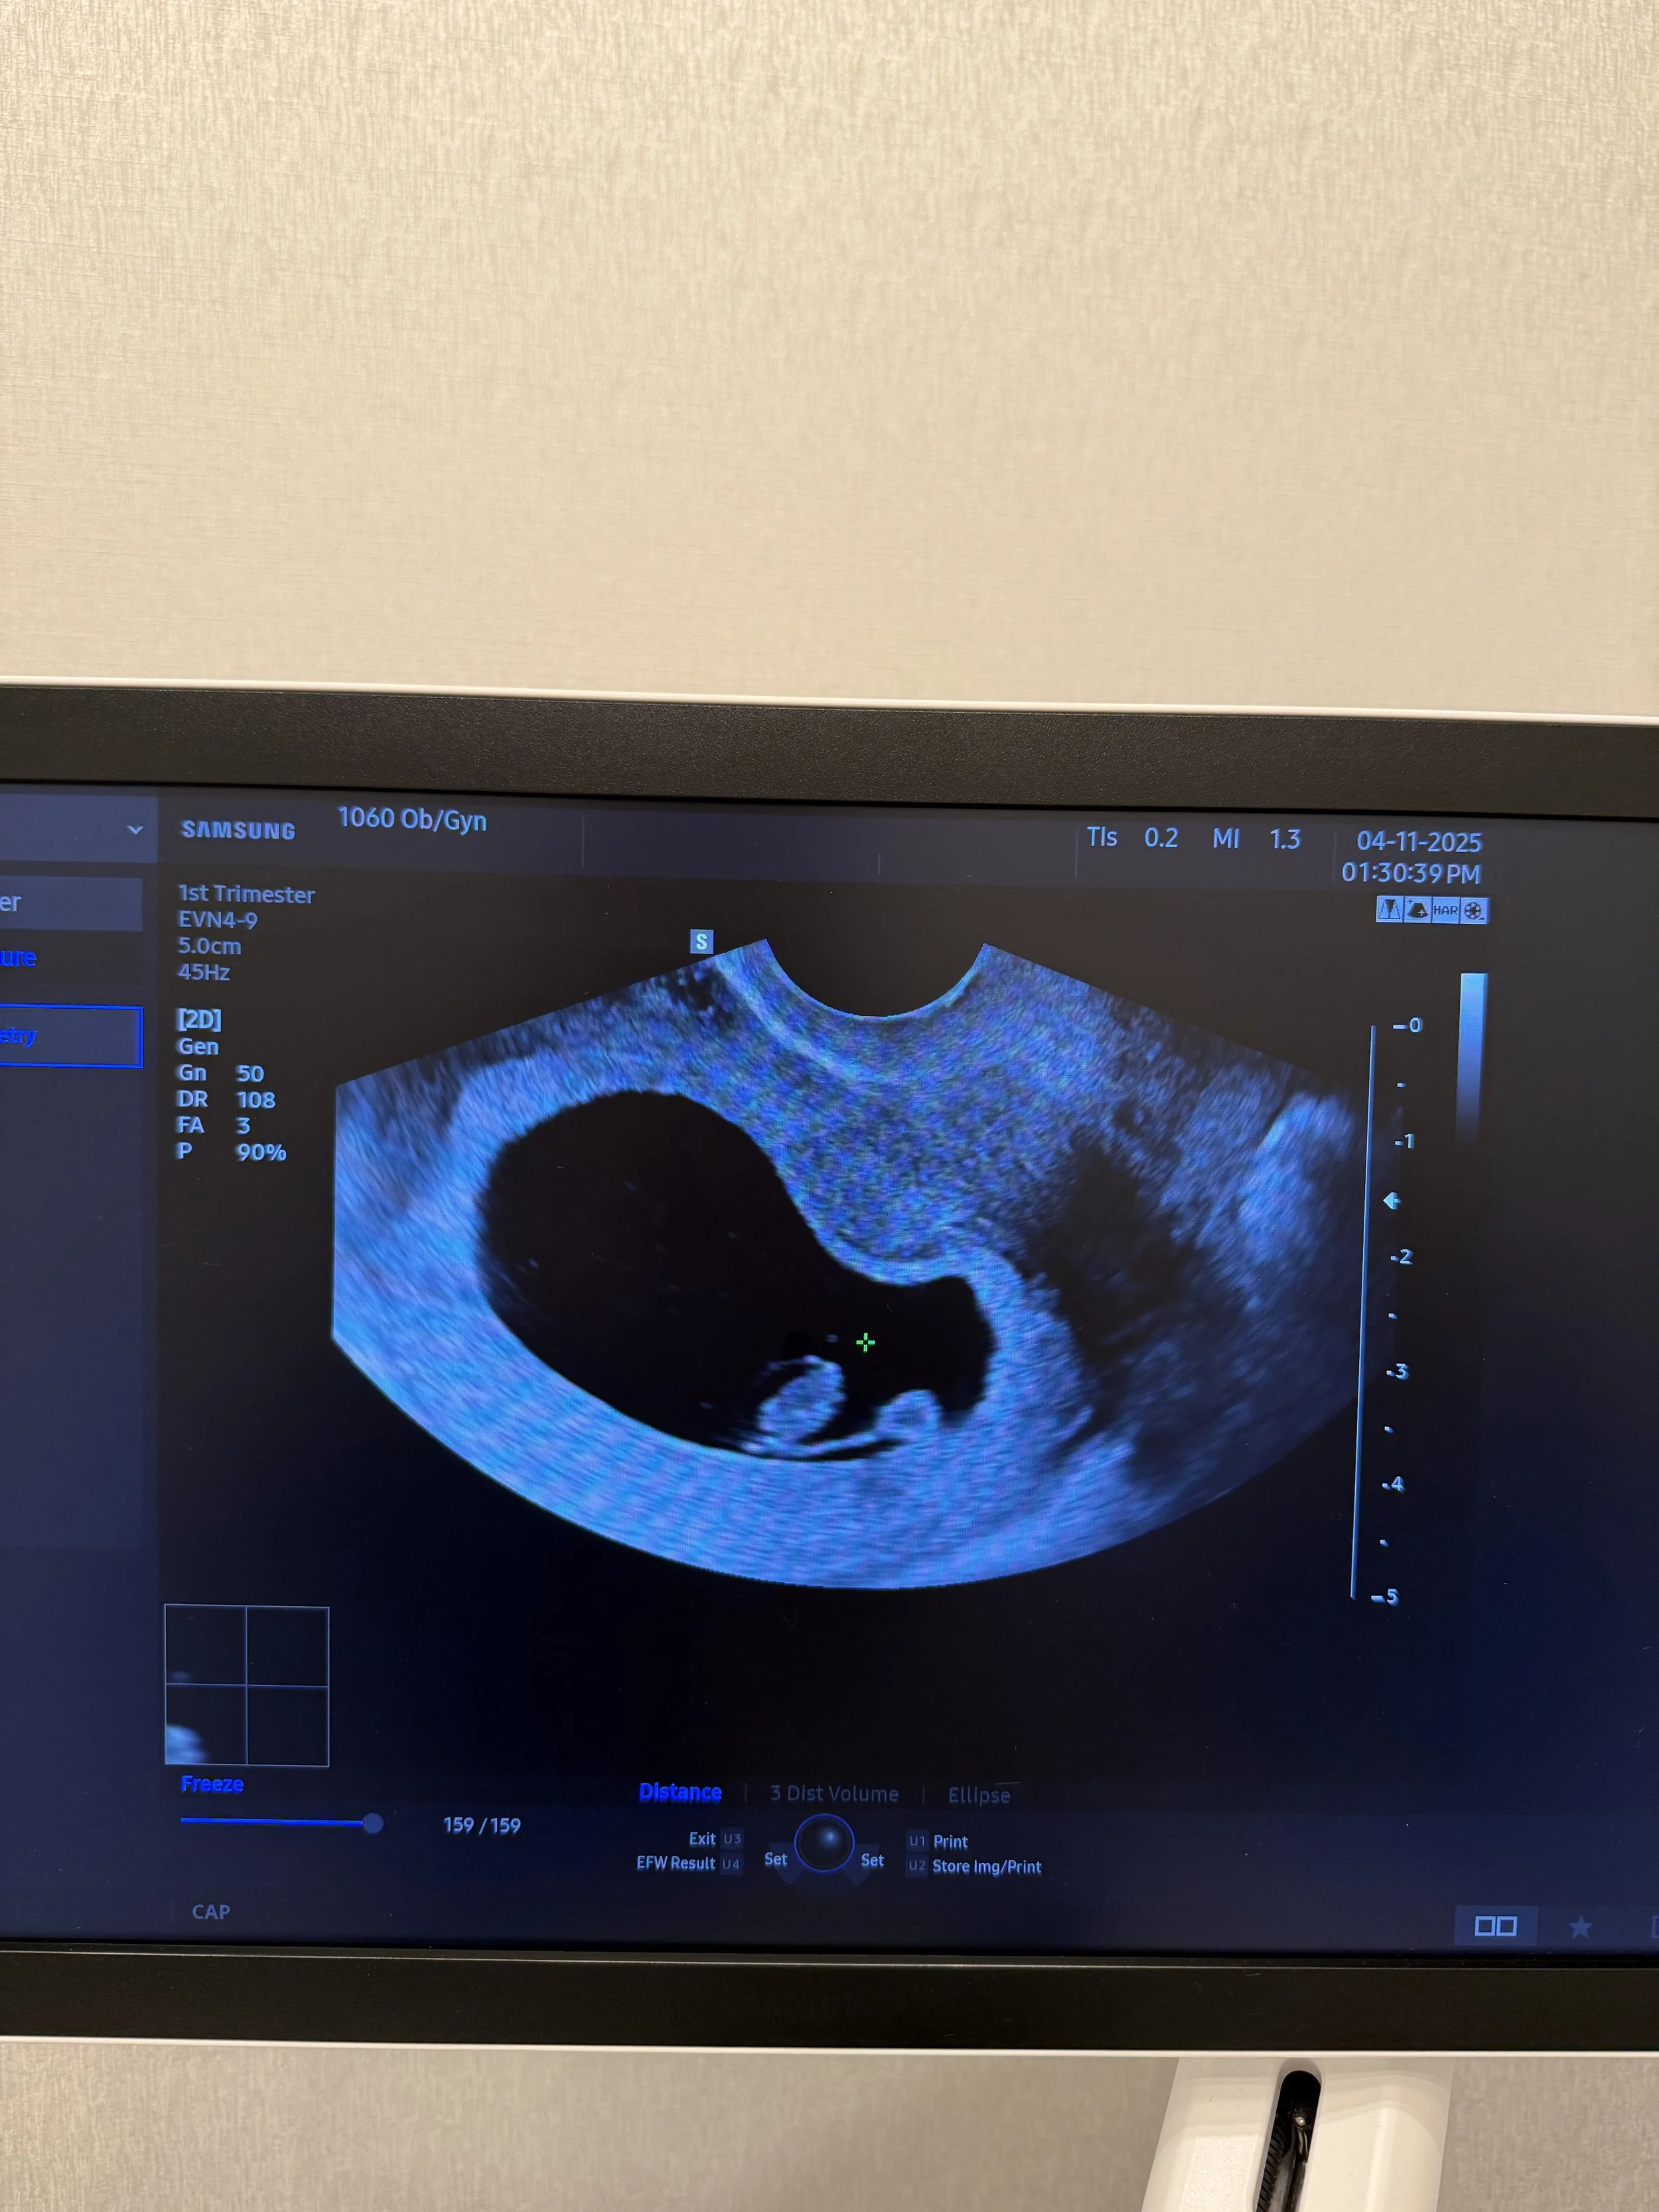

At our 8 week appointment I returned for another ultrasound, this time to hear the baby’s heartbeat. It was a critical moment. The Doctor didn’t waste time, knowing I was anxious as I was gripping Ryan’s hand. Moments later we heard our baby’s heartbeat for the first time. It was the most beautiful sound in the world. Strong and fast, and powering this little tiny life. The baby was starting to take shape.

Time between scans still built anxiety for me, but the closer I got to the 2nd trimester, the less anxious I felt. With so many wonderful things happening in our lives at once, the weeks seemed to fly by, and suddenly I was at my 12 week scan at our hospital.

It was starting to feel real!